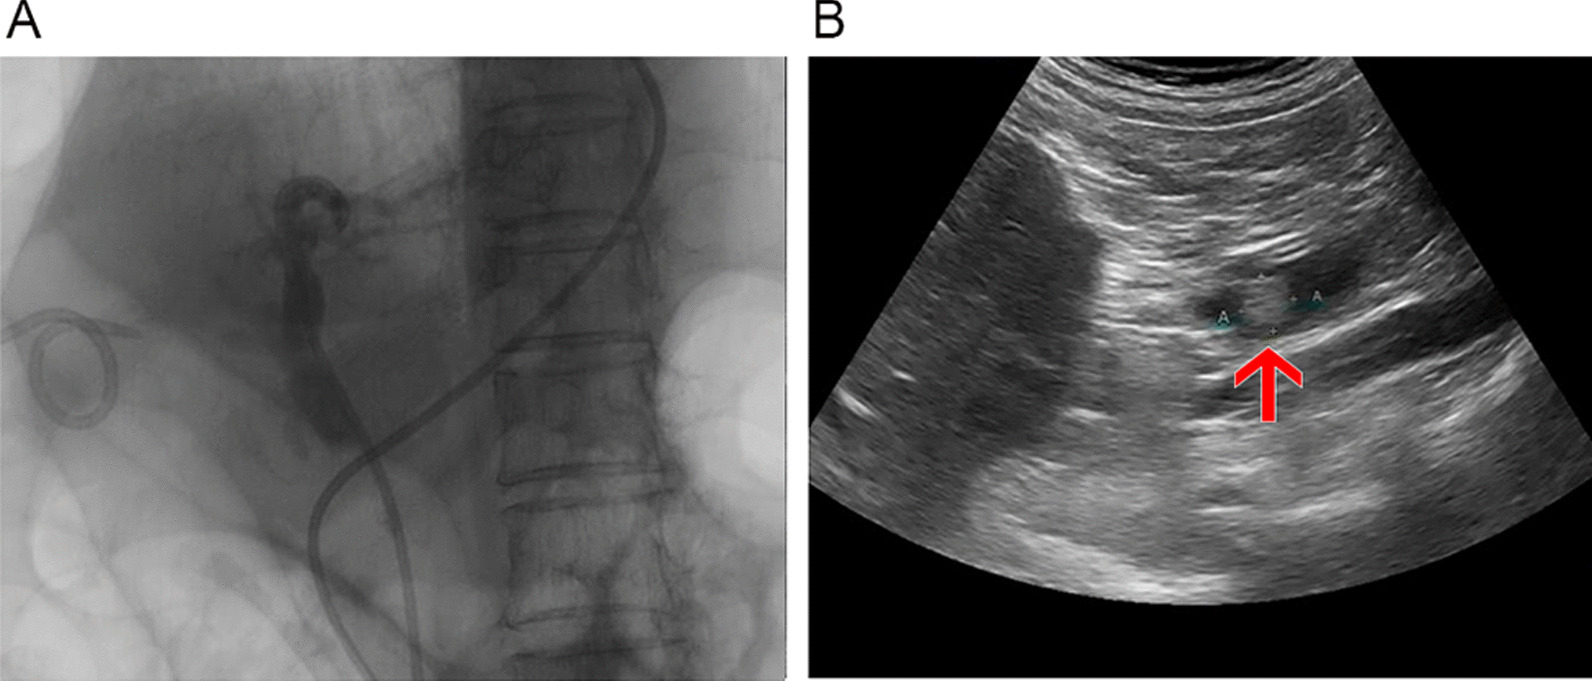

Of the 302 patients studied, there were 26 true positives, 246 true negatives, 5 false positives, and 25 false negatives by occlusion cholangiography (specificity, 98.0%; sensitivity, 50.9%; false-positive rate, 2.0%; false-negative rate, 49.1%). By comparison, ENBD-based saline-injection US imaging yielded 46 true positives, 247 true negatives, 4 false positives, and 5 false negatives (specificity, 98.4%; sensitivity, 90.1%; false-positive rate, 1.6%; false-negative rate, 9.9%), indicating significantly greater sensitivity (p < 0.001) and a significantly lower false-negative rate (p < 0.001). The two examinations did not differ significantly (p = 0.689) in terms of specificity and false-positive rate; although imaging of CBD length by saline-injection US performed better than that of occlusion cholangiography (p < 0.001), CBD diameter showed no statistical difference (p = 0.601) (Table 2). A comparison of imaging effects between occlusion cholangiography and ENBD-based saline US is shown in Fig. 3.

In routine US examinations of the 302 patients studied, there were 12 true positives, 250 true negatives, 1 false positive, and 39 false negatives (specificity, 99.6%; sensitivity, 23.5%; false-positive rate, 0.4%; false-negative rate, 76.5%). Again, ENBD-based saline-injection US significantly outperformed routine US, demonstrating higher sensitivity (p < 0.001) and a lower false-negative rate (p < 0.001), whereas specificities and false-positive rates did not differ significantly (p = 0.249). CBD imaging rates (p < 0.001), lengths (p = 0.048), and diameters (p = 0.034) also differed significantly (Table 3), with higher magnitudes displayed by saline-injection US. A comparison of the imaging effects of routine US and ENBD-based saline US is shown in Fig. 4.